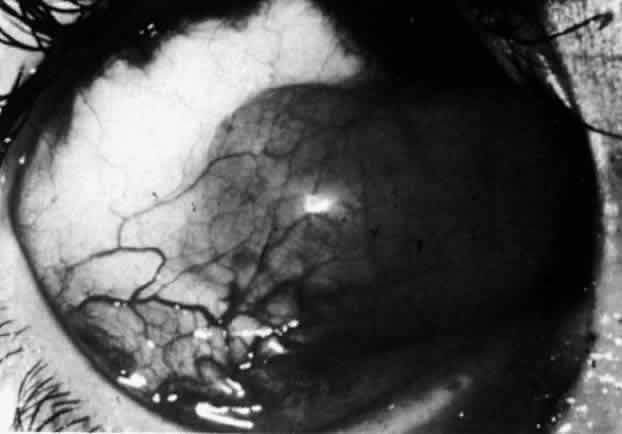

The characteristic features of necrotizing scleritis on fluorescein angiography are hypoperfusion and, eventually, nonperfusion of the vascular networks (Figs. 40 through 43).26 The initial changes are on the venous side of the capillary network; the transit time of the dye increases even if the eye is red and congested. If the disease process persists or has been present for a long time, thrombosis and permanent vaso-occlusive changes occur. These vessels (or the occluded capillary network) are bypassed by the opening of anastomotic channels. New vessels in a granuloma give rise to deep intrascleral leakage of dye (see Fig. 43). Conjunctival and episcleral involvement by the destructive change is late but is always preceded by vaso-occlusive changes that can sometimes be detected with use of the red-free light on the slit lamp (Figs. 44 and 45).

The redness of simple episcleritis may be intense, varying from a fiery-red or a brick-red discoloration to a mild red flush, but it does not have the bluish tinge that is seen in scleritis. The distribution is usually sectorial but can involve the whole anterior segment of the globe. The episcleral vessels are engorged but retain their normal radial position and architecture (Figs. 13 and 14; Color Plate 1A). In simple episcleritis, there is a diffuse edema of the episcleral tissues. These tissues are sometimes infiltrated with gray deposits that appear yellow in red-free light. Surprisingly, the eye is rarely tender to the touch.